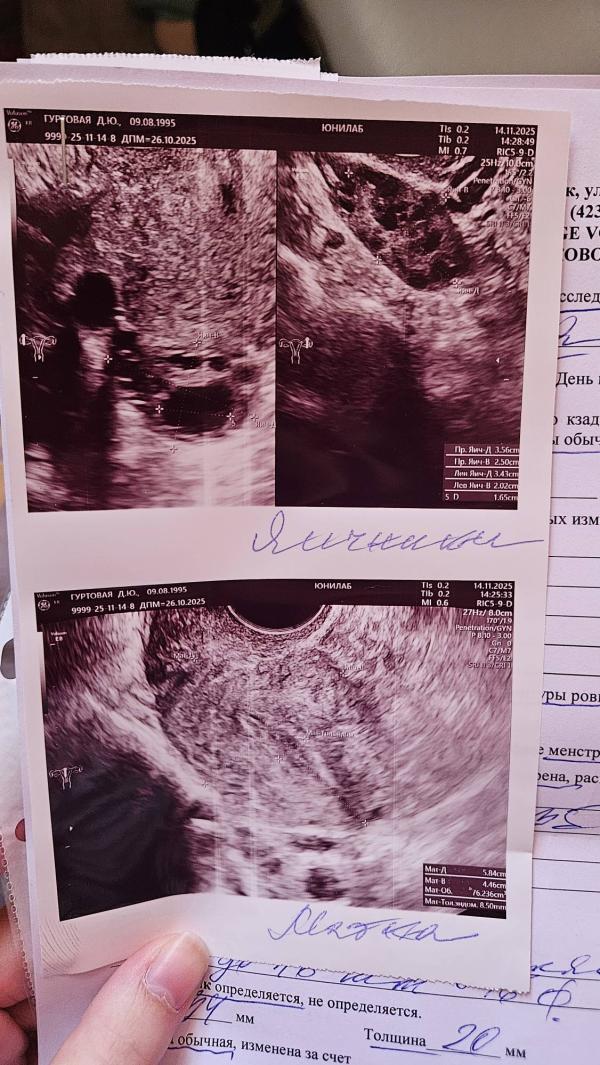

Итак, 20дц а овуляция только на подходе, странно...

У вас уже со дня на день овуляция и эндометрий хороший🙏🏻👌🏼